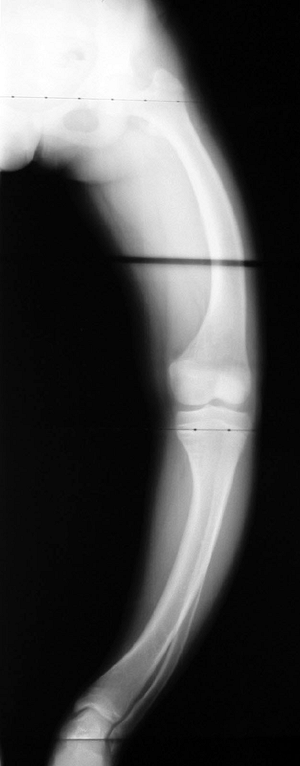

Figure 15-6

Radiograph of a young patient with osteogenesis imperfecta. (From

Baitner AC, Maurer SG, Gruen MB, et al. The genetic basis of the

osteochondrodysplasias. J Pediatr Orthop 2000; 20:594–605.) -

Classical findings: bone fragility, long bone deformities (Fig. 15-6)

-

May also have blue sclerae, dentinogenesis imper-fecta, and scoliosis

Osteoporosis

Multiple fractures

Bowing of long bones (often described as “gracile”)